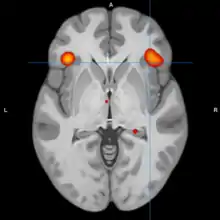

Bilaterally reduced activity in the inferior frontal gyrus (BA47).[69] Image at Talairach z=2

Regardless of mood state, during response inhibition tasks, people with bipolar disorder underactivate the right inferior frontal gyrus. Changes specific on euthymia include hyperactivations in the left superior temporal gyrus and hypoactivations in the basal ganglia, and changes specific to mania include hyperactivation in the basal ganglia.[76] A meta analysis of fMRI studies reported underactivations in the inferior frontal gyrus and putamen and hyperactivation of the parahippocampus, hippocampus, and amygdala. State specific abnormalities were reported for mania and euthymia. During mania, hypoactivation was significant in the inferior frontal gyrus, while euthymia was associated with hypoactivation of the lingual gyrus and hyperactivation of the amygdala.[69]